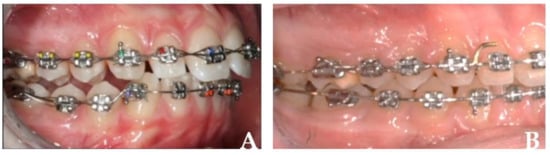

Figure 3. Multibracket appliance during curve of Spee leveling: (A) at the beginning of the treatment; (B) at the end of the treatment.

Fixed orthodontic multibracket appliance (Figure 3) may be useful to level the curve of Spee more than aligners because aligners’ “bite block” effect can produce posterior teeth intrusion or not allow posterior teeth extrusion. This effect can be reduced by the application of precision bite ramps on palatal upper anterior teeth [26,27,28,29]. If a deep bite can be solved just with upper and lower anterior teeth proclination and relative intrusion, aligners can perform like fixed appliances. If the treatment has the objective to intrude lower incisors and extrude posterior teeth, aligners have some difficulty making it possible [30,31].